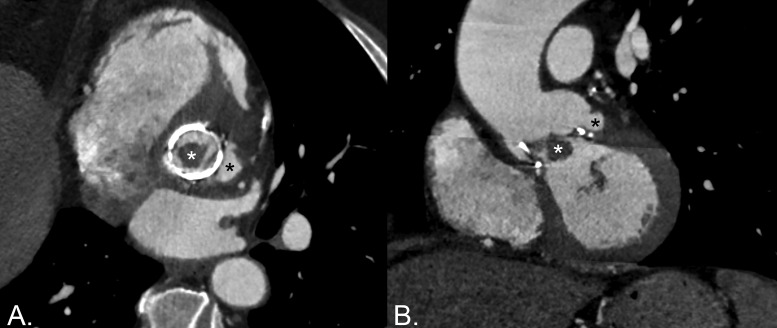

教学要点:心脏计算机断层血管造影对有经食管超声心动图(TOE)禁忌症的假瓣膜感染性心内膜炎患者特别有价值,或当TOE因严重钙化或假瓣膜而受到限制时,对检测脓肿和假性动脉瘤至少具有同等的灵敏度。

Teaching point: Cardiac computed tomography angiography is particularly valuable in patients with prosthetic valve infective endocarditis who have contraindications to transesophageal echocardiography (TOE), or when TOE is limited by heavy calcifications or the prosthetic valve, offering at least equivalent sensitivity for detecting abscesses and pseudoaneurysms.